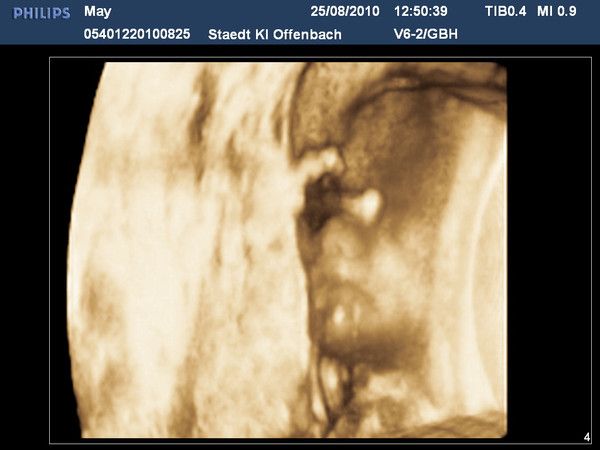

Unser Dezemberbaby

06.12.2010